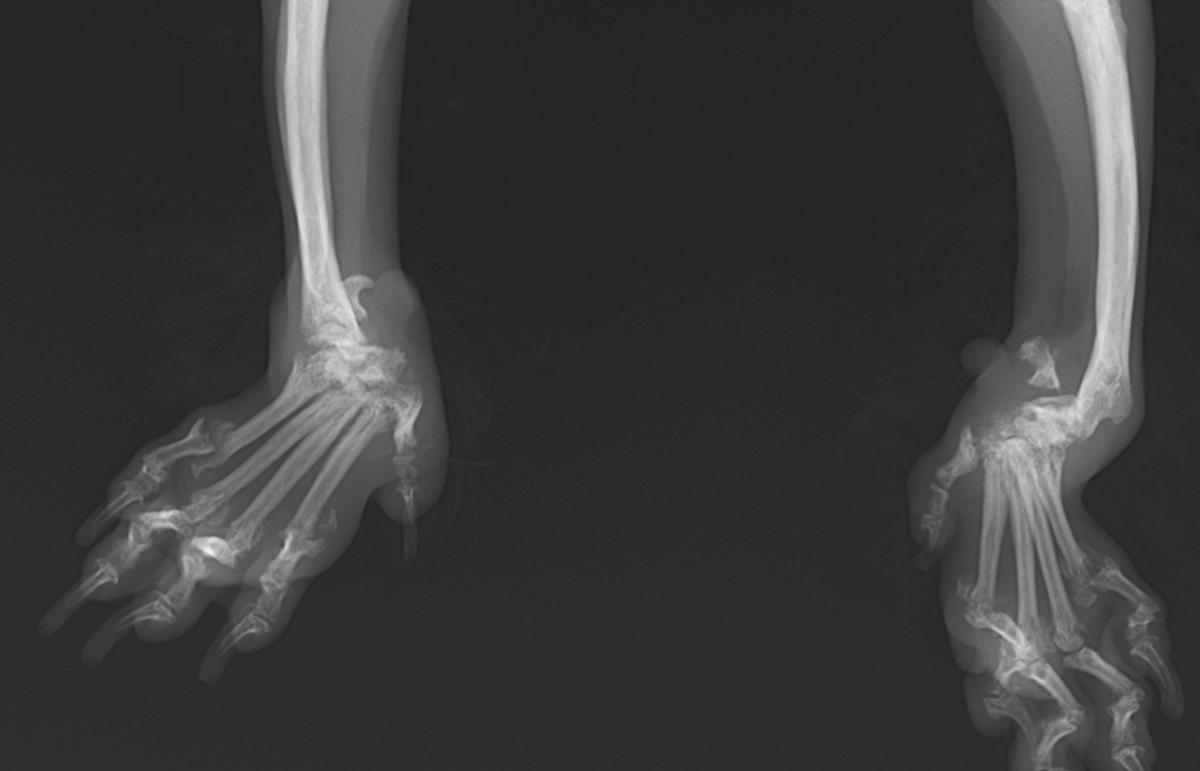

レントゲンを撮ってみると、手根関節を形成する多数の手根骨が溶解し、関節が変形してしまっていました。